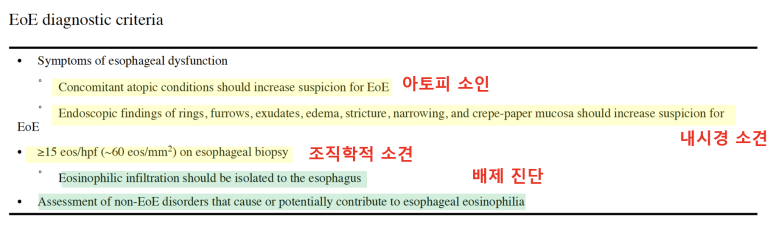

조직검사는 유럽의 경우 6개소를 시행할 것을 권고하고, 미국의 경우 2-4개의 promixal, distalesophagus에서 시행할 것을 권고하고 있습니다.진단 기준 상의 내용을 종합하여 호산구 식도염의 진단 기준을 확인하게 됩니다.먼저 전 세계에서 모여 만든 AGREE 컨퍼런스에서는 식도의 Dysfunction이 발생하는데 아토피 소인이 있고 내시경적으로 특징적인 소견이 있으며 조직학적으로 HPF당 15개의 호산구가 확인되어야 합니다. 이때 중요한 것은 호산구의 침착이 식도에만 국한되어야 하며 다른 2차적인 원인에 의해 식도 내 호산구가 증가하지 않는 것입니다. 즉, 다른 질환 없이 식도로만 호산구가 증가한다는 것을 의미합니다.

예를 들어 Achalaisa, 약물유발성식도염, 감염, GERD에 의해서도 호산구가 증가할 수 있으나 이러한 질환이 함께 발생할 경우에는 호산구식도염으로 진단할 수 없습니다.

즉, 식도 관련 증상이 있을 경우 내시경을 실시하고 조직검사에서 HPF당 15개 이상의 호산구가 있을 경우 식도 내에 호산구를 증가시키는 질환이 모두 제거된다는 가정 하에 호산구 식도염이라는 진단명을 붙일 수 있습니다.